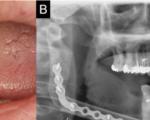

Severe maxillary and mandibular atrophy presents significant challenges in prosthetic ..

Juvenile ossifying fibroma (JOF) is a rare benign fibro-osseous tumor that predominantly affects ..